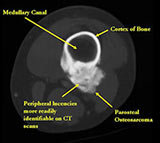

MRI/CT:

- Useful for determining medullary invasion

- Can help discern areas that may be high grade

- Most useful for evaluating the local extent of the tumor and relationship to neurovascular structures the circumference of the femur involved by the tumor (important for surgical planning)

- Appears to have broad attachment to underlying cortex with a cleft between exophytic base and cortex at periphery. This is referred to as a “String Sign” (cleft is often only identifiable on CT scan)